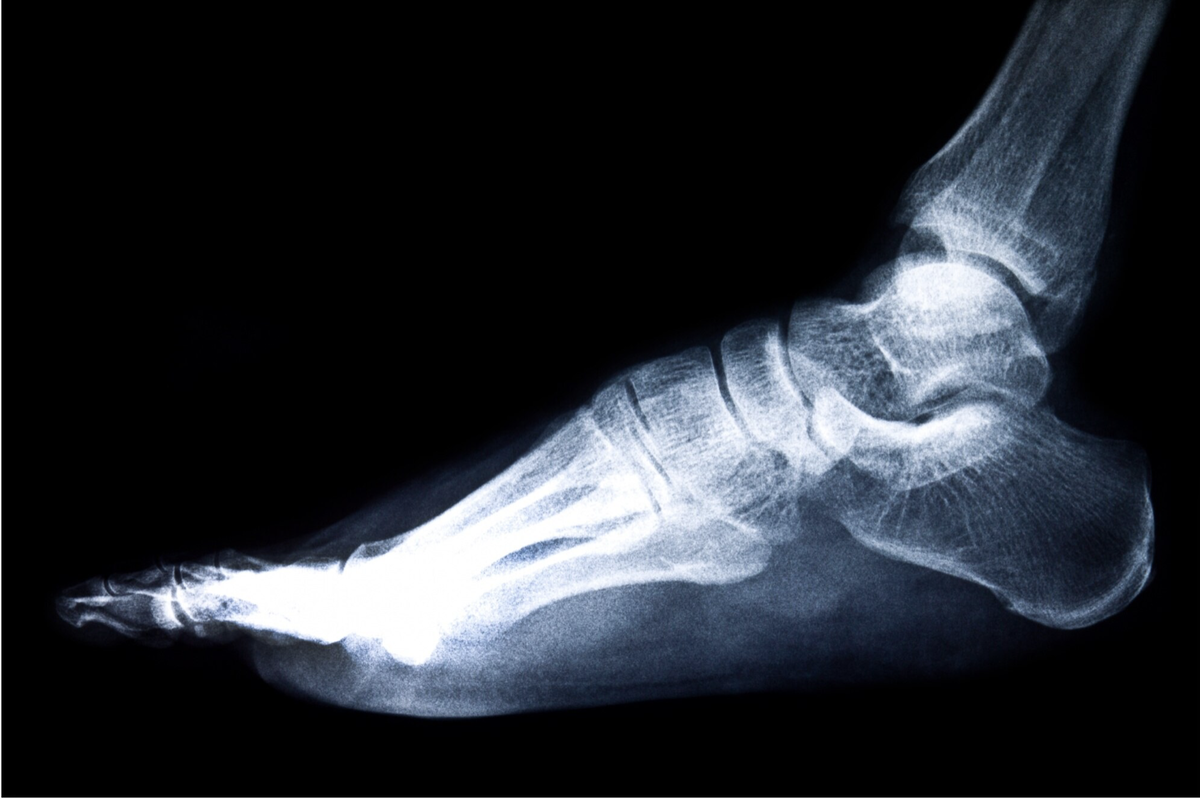

Как известно, наиболее важной состовляющий в биомеханике ходьбы, является стопа.

Она поддерживает вес всего тела. При прыжке и беге нагрузка составляет 200-300 и более килограмм.

Сооственно, при неправильной ее анатомиии, а также дискомфорте при ходьбе меняется вся фаза движения, что начинает влияет на все выше расположенные структуры. Стопы — фундамент нашего здоровья! Они выполняют важнейшие функции: